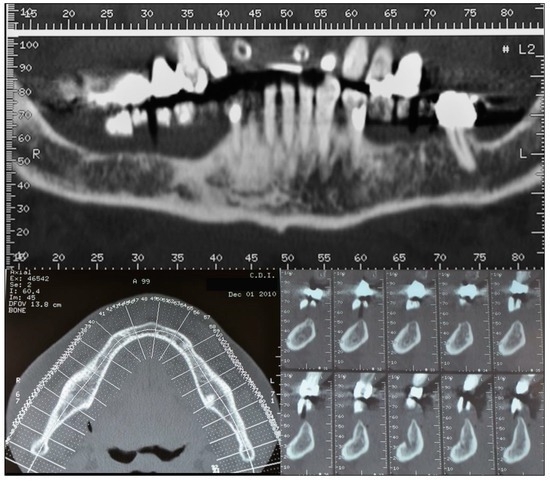

2. Case Description